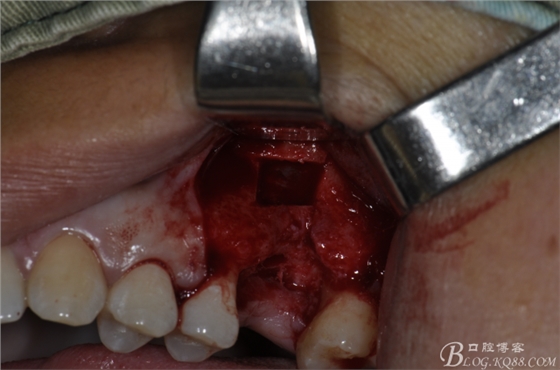

術(shù)中照片。

超聲骨刀切開骨外板 上頜竇外提一例